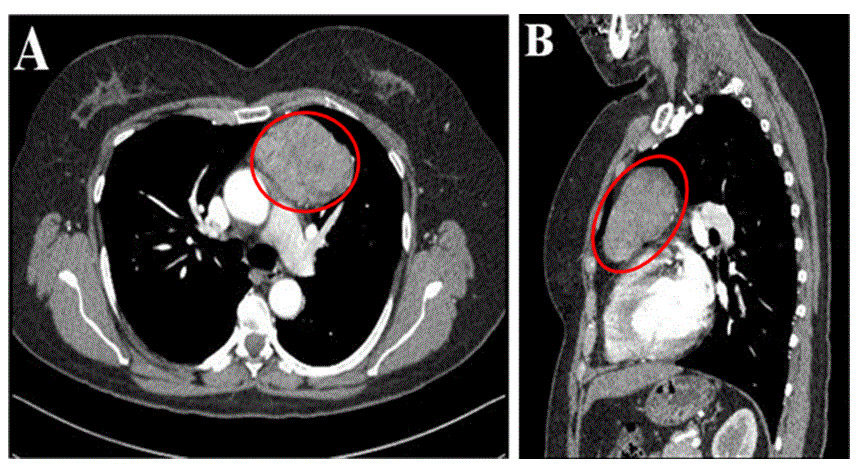

Saiba maisTimoma

Timoma é um tumor raro que se desenvolve no timo e apresenta graus diferentes de…